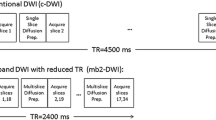

To investigate the potential utility of L1-DWI in terms of reduced acquisition time or improved spatial resolution, two different types of L1-DWI protocols were used:

During the first half of the study period (November through December 2019), patients underwent conv-DWI plus L1-DWI, where CS-based reconstruction was used to reduce acquisition time of conv-DWI (group A); during the second half of the study period (January through February 2020), CS-based reconstruction was invested to improve spatial resolution compared with conv-DWI (group B). Accordingly, in group A, L1-DWI was acquired with the same spatial resolution as conv-DWI, but faster; in group B, L1-DWI were acquired with similar acquisition time as conv-DWI but had a higher spatial resolution. In both patient groups, the same acceleration factor of 3 was applied as in healthy volunteer exams.

Liver DWI was performed before contrast media injection. For acquisition 2D multi-slice spin-echo single-shot EPI with respiratory belt triggering was used for both L1-DWI and conv-DWI. For L1-DWI acquisition, a moderate acceleration factor of 3 was applied based on empirical data from other clinical studies in anatomical imaging and volunteer results prior to the current study3,9. This provided relatively shorter EPI train length, echo time, and repetition time, compared to those in conv-DWI (acceleration factor 2), and resulted in a slightly reduced nominal scan time. For conv-DWI reconstruction, conventional SENSE was applied to the undersampled data. In addition to that, scan parameters of both sequences were matched as closely as possible, with shortest possible repetition times and same number of slices in the interleaved order in each case. For L1-DWI reconstruction, a regularized, iterative L1-norm minimization was applied assuring image sparsity in the wavelet domain and data consistency, as in typical CS reconstruction by taking the SENSE coil information into account20,21,26,28. Standard denoising was applied (Supplemental Digital Content 2). Image reconstruction was CPU-parallelized on the standard MR console computer (64 GB RAM, Intel Xeon E5–1620 CPU). Images were stored in the hospital database. Detailed MRI parameters of conv-DWI and L1-DWI for both volunteers and patient groups are listed in Table 1.